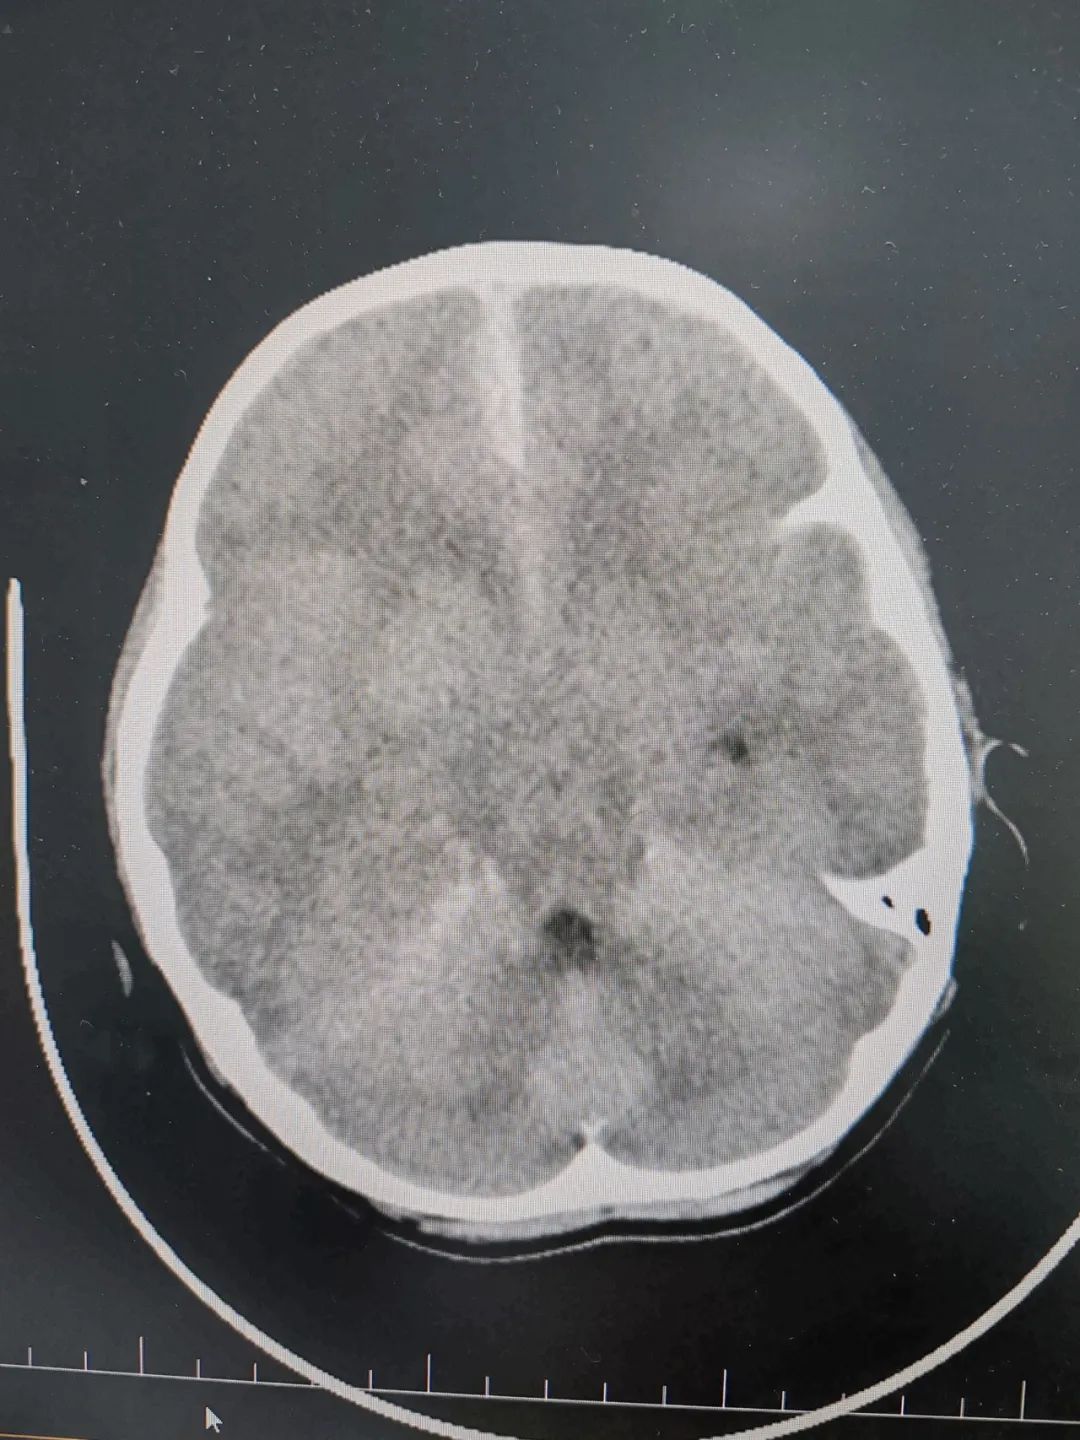

急诊CT提示:少量蛛网膜下腔出血、大脑镰旁见血肿影、颅内板下多发薄层血肿、多发脑挫伤并小血肿形成待排、颅内积气、颅骨多发骨折、蝶窦壁骨折并蝶窦内少量积血待排、腹腔及肺部多处损伤等。入院后,小女孩陷入深昏迷状态,双侧瞳孔散大。神经外科主任徐学敏为其行去骨瓣减压手术,手术顺利,但术中出血量大,小女孩特殊的“熊猫血”血型,让救治难度倍增。